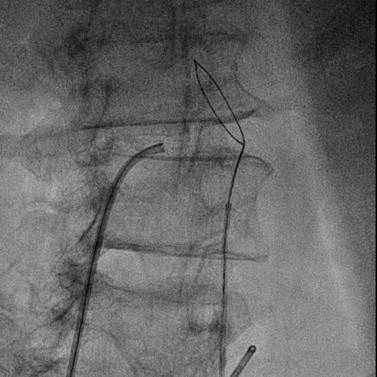

经右股静脉置入7F JR指引导管至下腔静脉,经右股动脉置入6F猪尾导管至腹主动脉,于下腔静脉及腹主动脉同时造影精确定位目标穿刺点。

穿刺系统与圈套器配合完成穿刺并建立下腔静脉至腹主动脉的通路